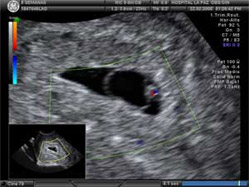

Al final de esta quinta semana se produce un nuevo hito en la vida del pequeño que se está empezando a formar: se desarrolla un primitivo corazón, el órgano que antes se va a formar.

"El corazón se empieza a formar a partir del 21 día de edad fetal. Sin este órgano el desarrollo del embrión es inviable. Inicialmente el corazón se forma de células que forman un tubo, como si fuera una cañería, un tubo recto y posteriormente se repliega sobre si mismo, como si fuera una U y rota. Así se forman las distintas cavidades del corazón. Eso ocurre hasta el segundo mes de gestación, en el que ya está completamente formado".

Pero, de momento, ese esbozo de corazón son dos tubos que cuentan con un latido rítmico, que proyecta unas células sanguíneas -no son glóbulos rojos- por los primeros vasos sanguíneos.